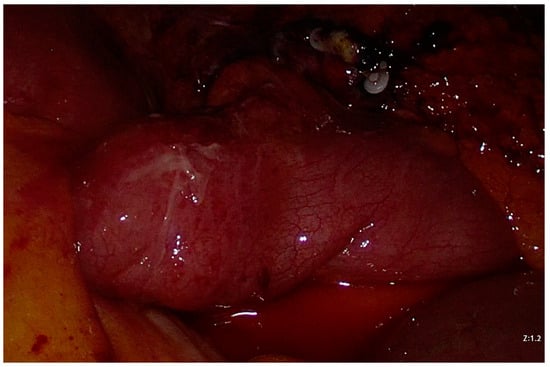

2. Case Presentation